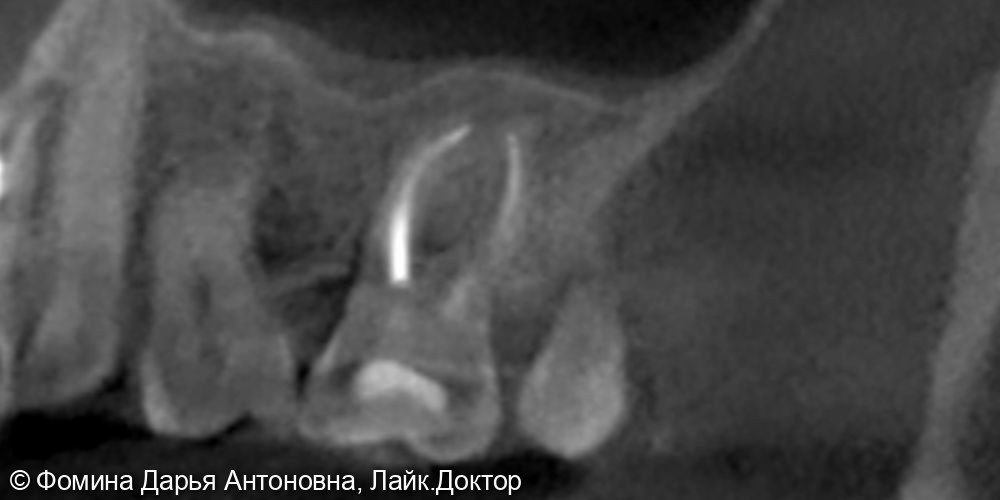

Зуб был пролечен около 5 лет назад в другой клинике и клинически не беспокоил. Однако при проведении КЛКТ выявили периапикальный очаг воспаления — скрытую инфекцию у верхушки корня.

Диагностика с помощью 3D-КТ: источник боли был обнаружен в 16 зубе – воспаление на верхушках корней. Зуб ранее лечили от кариеса более 5 лет назад.